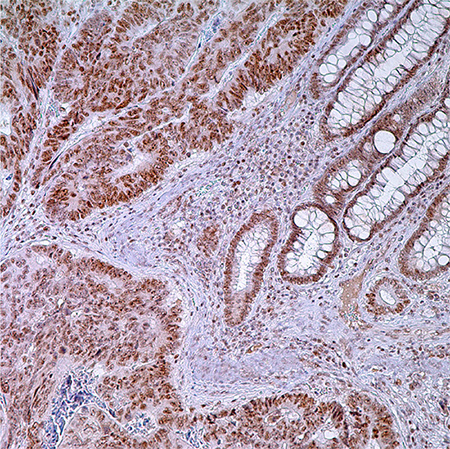

图 1.PMS2 (EPR3947†) -结肠腺癌注:固有层中腺细胞,普通隐窝细胞和淋巴细胞核酸标记。

大多数的诊断解剖病例实验室都很容易进行IHC检测。可以购买到LS相关的4个蛋白抗体(通过相关基因的种系突变)。一类不正常的结果是一个或多个肿瘤中的蛋白核免疫反应活性完全缺失。所有4个蛋白在非肿瘤组织中正常表达。因此,间质、淋巴细胞和非肿瘤性隐窝是重要的内参。抗原回收步骤是很重要的;在一项研究中,不充分的抗原回收和染色不够以及LS低特异性有关(然而高背景染色会导致低灵敏度)。98染色不够和异质染色经常发生,这可能是组织固定不均匀或其他技术因素造成的。在这些案例中,重复进行IHC可能有帮助。在林奇筛查中使用IHC的一个关键优势是它能够指导基因测试。MSH2功能丧失(因为缺失突变),MSH2和MSH6的免疫组织化学(IHC)不表达;而如果是MLH1功能丧失(因为缺失突变或启动子过度甲基化),就会出现MLH1和PMS2免疫组织化学不表达。单纯的MSH6或PMS2蛋白缺失说明对应各自基因发生了突变。